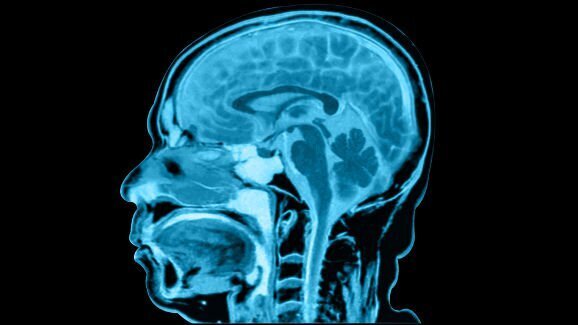

Според д-р Бърджес най-очевидното обяснение за състоянието на мъжа би могло да бъде форма на антероградна амнезия. Това означава, че е увреден хипокампусът – участък от мозъка, отговарящ за превръщането на информация от кратката първична памет в дълготрайна вторична, и спомените не могат да бъдат формирани и съхранявани правилно. Въпреки това данните от мозъчните скенери на мъжа не сочат отклонения. В такъв случай е възможно причината да се крие в психогенно заболяване. Д-р Бърджес провел подробни психиатрични тестове, за да определи дали мъжът е претърпял травма, но установил, че пациентът е емоционално здрав. Това било потвърдено от неговата съпруга, според която до посещението при зъболекар през 2005 г. в живота на мъжа й не е имало травмиращи събития.